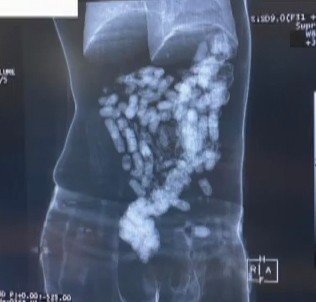

Kontrollere devam eden ekipler, yolcuların karın bölgesinde olağandışı bir sertlik saptadı. Bunun üzerine H.F. ile R.Y., havalimanlarında kullanılan "yutucu tespit cihazı" ile kontrol edildi. Ardından röntgenleri çekilen yolcuların uyuşturucu kuryesi oldukları ve içlerinde uyuşturucu olan daralı ağırlığı 2 kilo 14 gramı bulan 244 adet kapsülü yuttukları ortaya çıktı. Tıbbi yöntemlerle çıkarılan uyuşturucu kapsüllerine el konulurken, R.Y. ve H.F. adlı 2 uyuşturucu kuryesi gözaltına alındı.